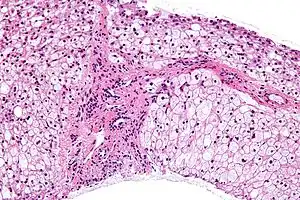

Pompe disease is 1 in 13,000.[10] | No | Yes | No | Muscle weakness, exercise intolerance, abnormal lysosomal glycogen accumulation in muscle biopsy. Late-onset Pompe may have a pseudoathletic appearance of hypertrophic calf muscles.[11]

Myopathy (including exercise-related fatigue, exercise intolerance, muscle weakness). Muscle biopsy shows glycogen accumulation.[25] |

Prolonged hypo- and hyperthyroid myopathy leads to atrophy of type II (fast-twitch/glycolytic) muscle fibres, and a predominance of type I (slow-twitch/oxidative) muscle fibres.[47][42][43] Muscle biopsy shows abnormal muscle glycogen: high accumulation in hypothyroidism and low accumulation in hyperthyroidism.[49][46][47] Hypothyroid myopathy includes Kocher-Debre-Semelaigne syndrome (childhood-onset), Hoffman syndrome (adult-onset), myasthenic syndrome, and atrophic form.[49]

In patients with increased growth hormone, muscle biopsy includes, among other features, excess glycogen deposition.[50]

Poor diet and malabsorption diseases (such as celiac disease) may lead to malnutrition of essential vitamins necessary for glycogen metabolism within the muscle cells. Malnutrition typically presents with systemic symptoms, but in rare instances can be limited to myopathy.[56] Vitamin D deficiency myopathy (also known as osteomalic myopathy due to the interplay between vitamin D and calcium) results in muscle weakness, predominantly of the proximal muscles; with muscle biopsy showing abnormal glycogen accumulation, atrophy of type II (fast-twitch/glycolytic) muscle fibres, and diminished calcium uptake by the sarcoplasmic reticulum (needed for muscle contraction).[57][58][59] Although Vitamin D deficiency myopathy typically includes muscle atrophy,[57] rarely calf muscle hypertrophy has been reported.[60][61]